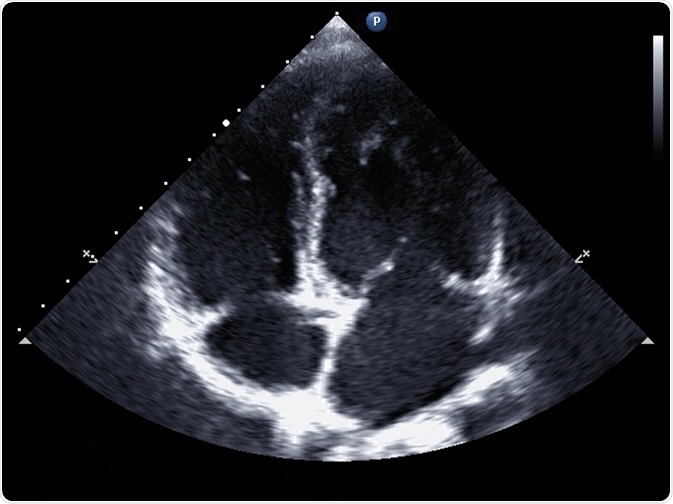

Standard transthoracic two-dimensional echocardiography in a patient with hypertension - picture by kalewa

In standard echocardiography, a black and white image is produced in real-time, allowing for an accurate assessment of chamber size and thickness.

The size of each ventricle can also be calculated to diagnose myocardial hypertrophy, a heart enlargement that more commonly affects the left ventricle and occurs in diseases such as heart failure. The 2-dimensional moving picture of the heart also allows the assessment of cardiac valve function and the identification of congenital disabilities.